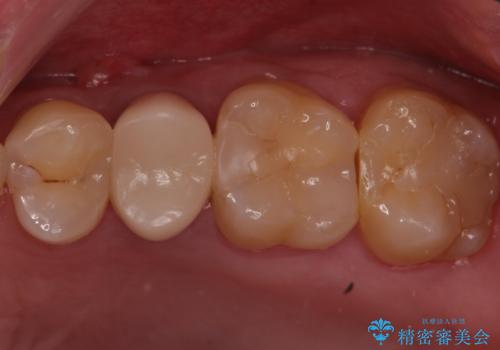

銀歯を白くして見た目を改善したい !

もげてしまった奥歯 オールセラミッククラウンでの補綴治療